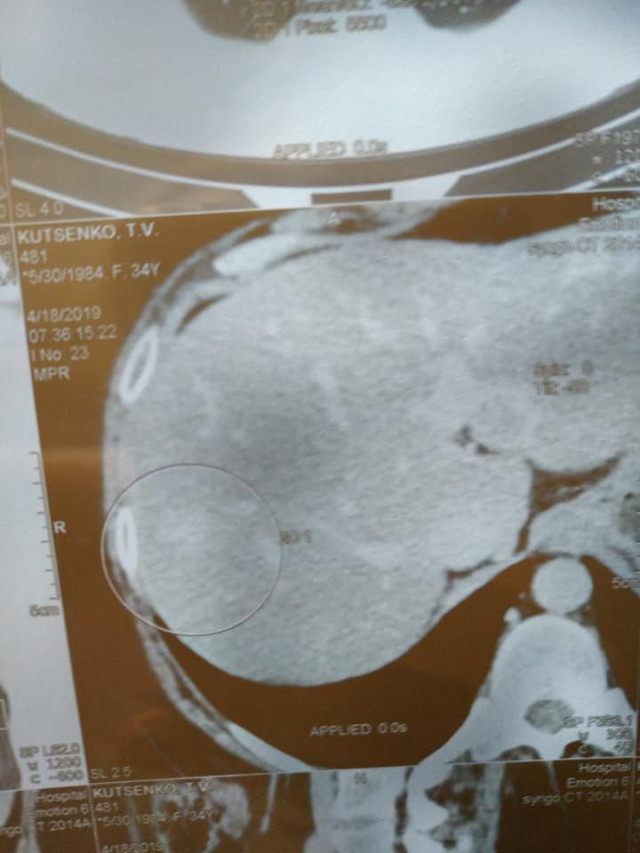

«Слава Богу, лікування допомагає, динаміка без змін у печінці, але сама структура стала з неоднорідної однорідною, так само в легенях – з ареолом матового скла. Це означає, що метастази перетворюються в щось типу фіброзу чи рубця. Зараз я узгоджую питання про їх видалення лапараскопічне, якщо це буде можливо. Потрібно їхати на консультацію до Києва», – написала жінка.

Нагадаємо, у жінки четверта стадія раку молочної залози. Вона лікується препаратом «Ібранс», на який потрібно 43 тисячі гривень у місяць.